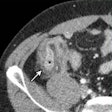

PET/CT rules supreme in cases of neuroendocrine tumors